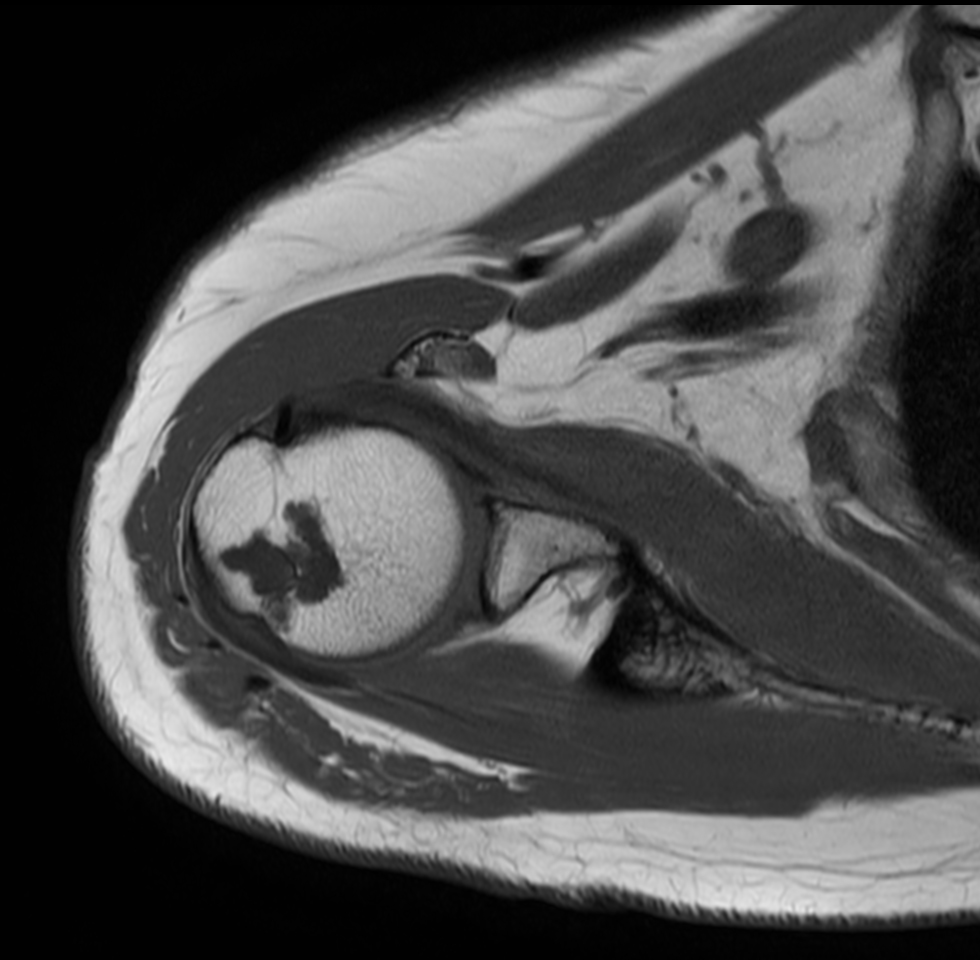

Axial PDw TSE